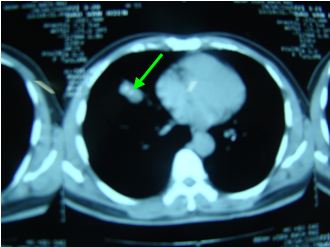

Chụp cắt lớp vi tính lồng ngực: Khối u thuỳ giữa phổi phải kích thước 26 ´ 13mm, không có hạch rốn phổi, trung thất.

Chụp cắt lớp vi tính lồng ngực

Trước điều trị: Hình ảnh khối u thuỳ phổi phải, kích thước 26x13mm

Sau điều trị: Không còn khối u, không có hạch trung thất